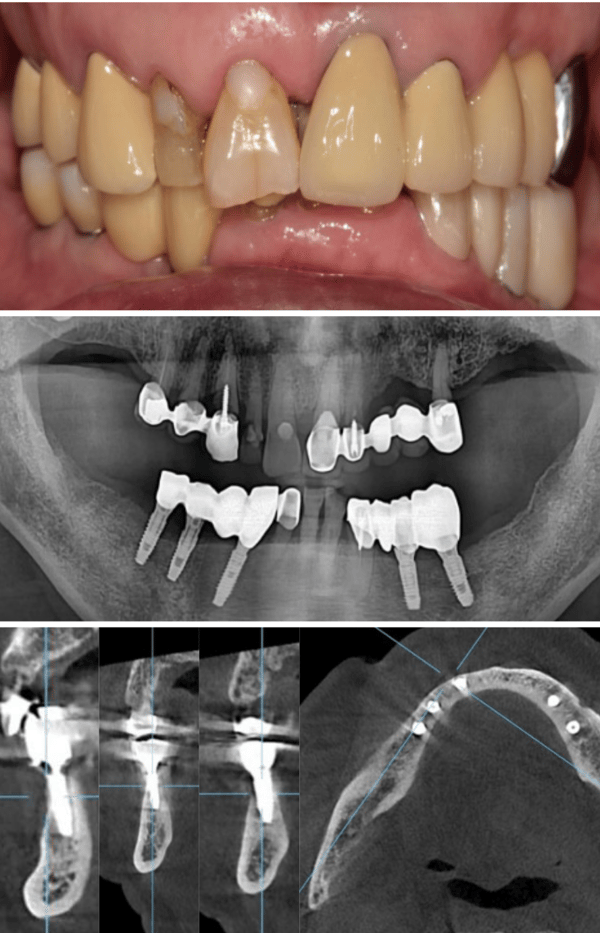

一位長期受牙齒問題困擾的病患走進了診間,他的下顎依賴著一副活動局部假牙維持僅存的咀嚼功能,而右下側的牙橋邊緣已出現繼發性齲齒,多顆牙齒根尖甚至出現病變。對於任何一位經驗豐富的醫師來說,這都是一個棘手的開局。病患渴望植牙,但他提出了一個令許多醫師頭痛的要求:受限於經濟與社交需求,他不願意拔除所有患牙,更不願意在漫長的治療期間經歷無牙的尷尬期。

就在第一階段治療開始五週後,計畫趕不上變化。病患那副原本就脆弱的 RPD 徹底斷裂,且已無法修復。這意味著病患面臨著徹底喪失咀嚼功能的風險,恐懼與焦慮瞬間籠罩了整個醫病關係。在傳統流程中,這通常代表著災難:你需要重新印模、重新製作臨時假牙,甚至被迫推翻原有的手術時程。

但在擁有完整數位工作流的診所裡,這卻是一個展示應變能力的絕佳時刻。Dr. Lee 迅速調整策略,決定提早啟動右側的治療,並大膽採用「導引式手術」搭配「立即受力」。這意味著病患將在手術當天就獲得固定的臨時贋復物,徹底告別活動假牙的夢魘。

經過兩個月的癒合期,從 X 光片中可以清晰看見,即便經歷了立即受力,植體周圍的邊緣骨依然穩定,毫無吸收跡象。這證明了數位導引手術在分散咬合力上的卓越表現。最終,醫師利用已經確認穩定的咬合記錄,透過數位印模製作了全鋯冠。當最終贋復物裝在病患口中,那種絲毫不差的密合度與無需反覆修磨的順暢感,正是數位全口重建最迷人的終點。